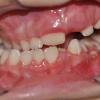

Appearance in infancyAppearance at the age of six yearsAppearance at the age of six, profileConvergence. Strong deviation of jawsDistraction osteogenesis of lower jaw.Distraction osteogenesis of lower jaw, profile.After distraction osteogenesis. The deficit of the soft tissues remains.After distraction osteogenesis, profile.

Craniofacial (Hemifacial) Microsomia is a relatively common disorder in which the lower half of one side of the face is underdeveloped and does not grow normally having as a result facial asymmetry or/and malformative development of certain organs. The degree of malformation varies from mild degree that is just perceived up to very severe degree. The organs that are commonly affected are the lower jaw (mandibular hypoplasia) and auricles. The upper jaw (maxillary hypoplasia) and the cheekbone are also affected but to a lesser extent. In milder forms, the problem may only be the underdeveloped auricles or be observed a small degree facial asymmetry.

In the most severe forms, the lower jaw may be very malformative or not developed at all at the side of the face with this disorder. The soft tissues are not developed properly giving to the face a very asymmetrical appearance.